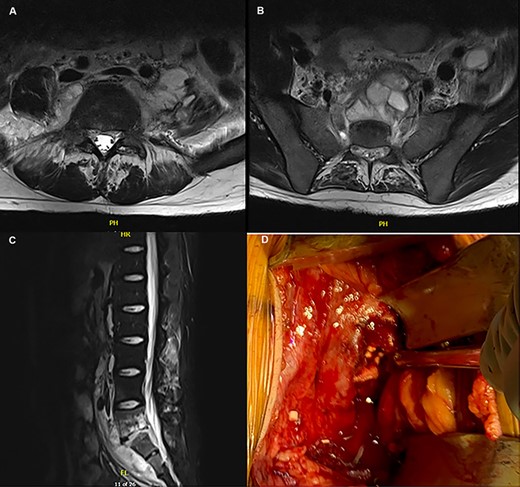

(A–C) MRI depicting the osteomyelitis, discitis and abscess involvement around L5/S1; (D) intraoperative picture of the L5/S1 disc space with placement of tobramycin antibiotic beads.

After 6 weeks of therapy, imaging showed progression of L5-S1 discitis/osteomyelitis and multiple abscess formations. He was admitted for a repeat incision and drainage through an anterior retroperitoneal approach with vascular, spine and acute care surgery. A large abscess was noted anterior to L5/S1, with the infection extending into the disc space. After drainage of the abscess and debridement, tobramycin antibiotic impregnated beads were placed in the disc space (Fig. 1D).